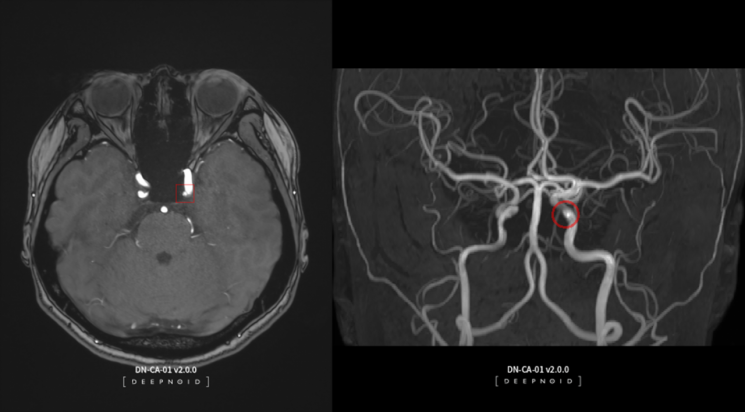

2008년 의료 AI 전문 기업으로 시작한 딥노이드 는 의료 분야를 넘어 산업·보안 영역으로 사업 범위를 넓히고 있다. 2021년 코스닥 시장에 입성했다. 사업군은 크게 의료 AI와 산업 AI로 나뉜다. 이 중 대표 제품으로 뇌동맥류 AI 영상 판독 솔루션인 딥뉴로(DEEP:NEURO)와 딥러닝 기반 머신비전 솔루션인 딥팩토리(DEEP:FACTORY)가 있다. 딥노이드의 주력이기도 하다.

딥뉴로는 뇌혈관 MRA(자기공명혈관조영술) 영상에서 뇌동맥류 의심 부위를 AI로 판독·분석해 진단을 보조하는 진단 솔루션이다. 2017년 기준 국내 연간 뇌혈관질환 환자수는 약 92만명에서 2021년 110만명으로 급증했다. 손 본부장은 "매년 건강검진을 받는 사람이 있는 만큼 매출이 꾸준히 발생할 수 있을 것으로 본다"며 "확진을 받은 사람이 110만명이지만 검사를 받는 사람까지 포함하면 매출 규모는 예상 대비 더 커질 수 있을 것"이라고 설명했다.